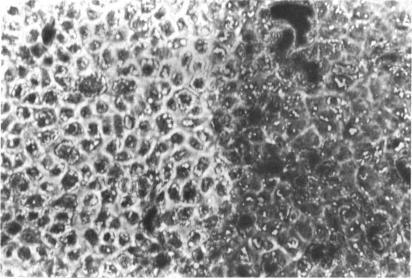

Three major pathologic processes caused by light in the primate retina: a search for mechanisms.

Trans Am Ophthalmol Soc. 1982;80:517-79.